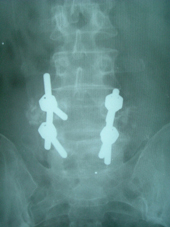

Cervical disc prolapses are treated by surgery in collaboration with Neurosurgeon. Cases of lumbar instability are treated by pedicle screw instrumentation and fusion

| Listhesis (Post op) |

Listhesis (Post op) |